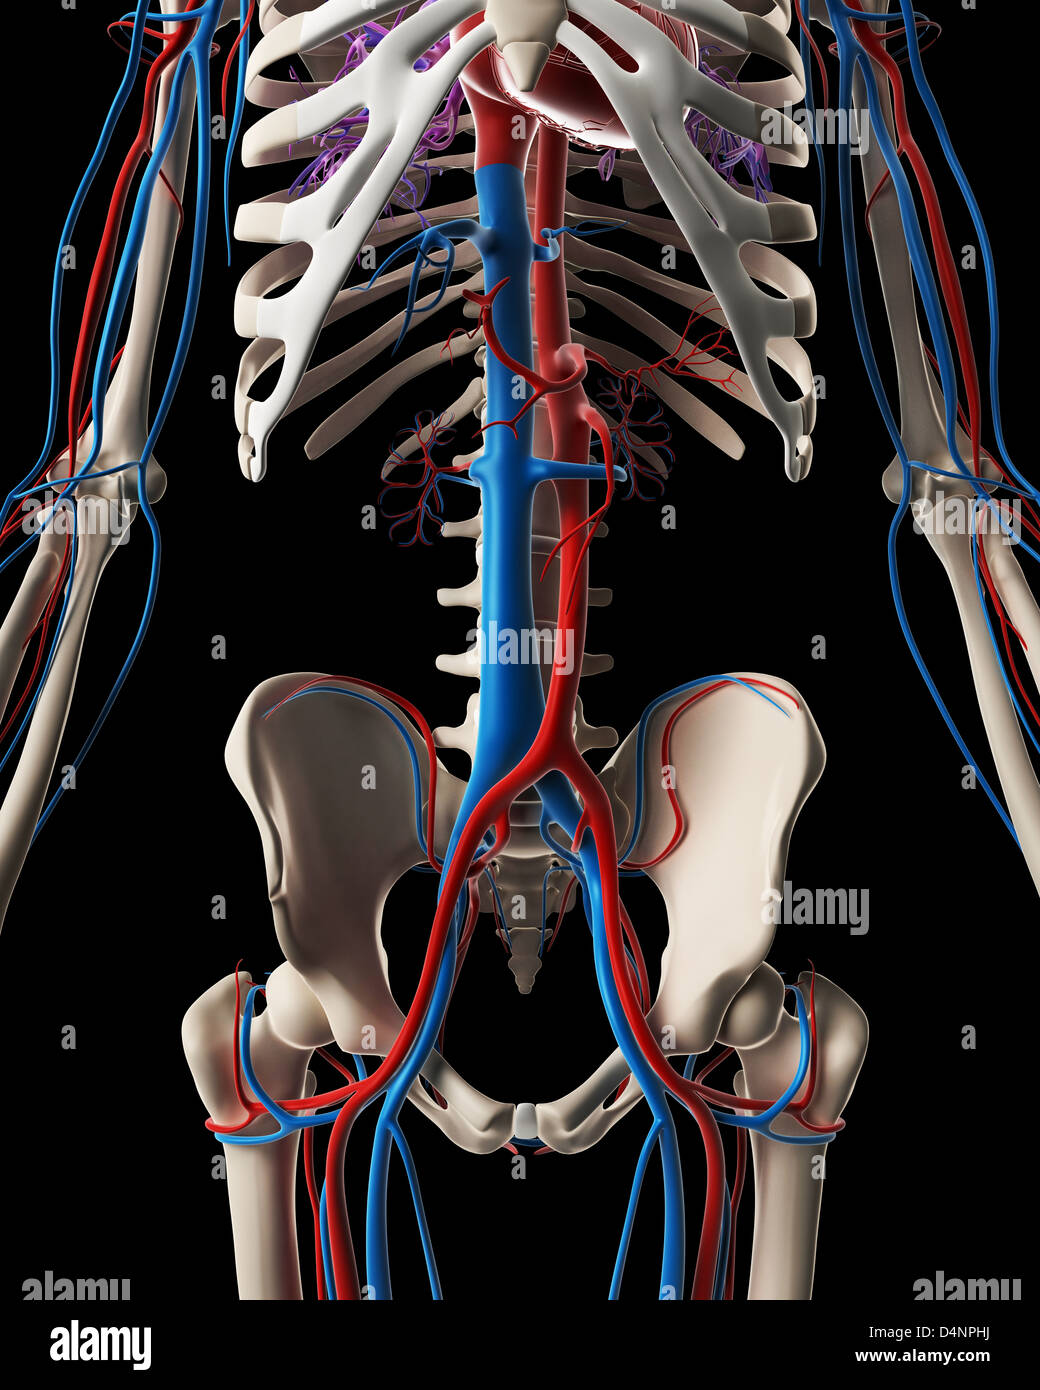

Vascular system Stock Photohttps://www.alamy.com/image-license-details/?v=1https://www.alamy.com/stock-photo-vascular-system-54568462.html

Vascular system Stock Photohttps://www.alamy.com/image-license-details/?v=1https://www.alamy.com/stock-photo-vascular-system-54568462.htmlRFD4NPHJ–Vascular system

Vascular system Stock Photohttps://www.alamy.com/image-license-details/?v=1https://www.alamy.com/stock-photo-vascular-system-54568186.html

Vascular system Stock Photohttps://www.alamy.com/image-license-details/?v=1https://www.alamy.com/stock-photo-vascular-system-54568186.htmlRFD4NP7P–Vascular system

Vascular system Stock Photohttps://www.alamy.com/image-license-details/?v=1https://www.alamy.com/stock-photo-vascular-system-54546602.html

Vascular system Stock Photohttps://www.alamy.com/image-license-details/?v=1https://www.alamy.com/stock-photo-vascular-system-54546602.htmlRFD4MPMX–Vascular system